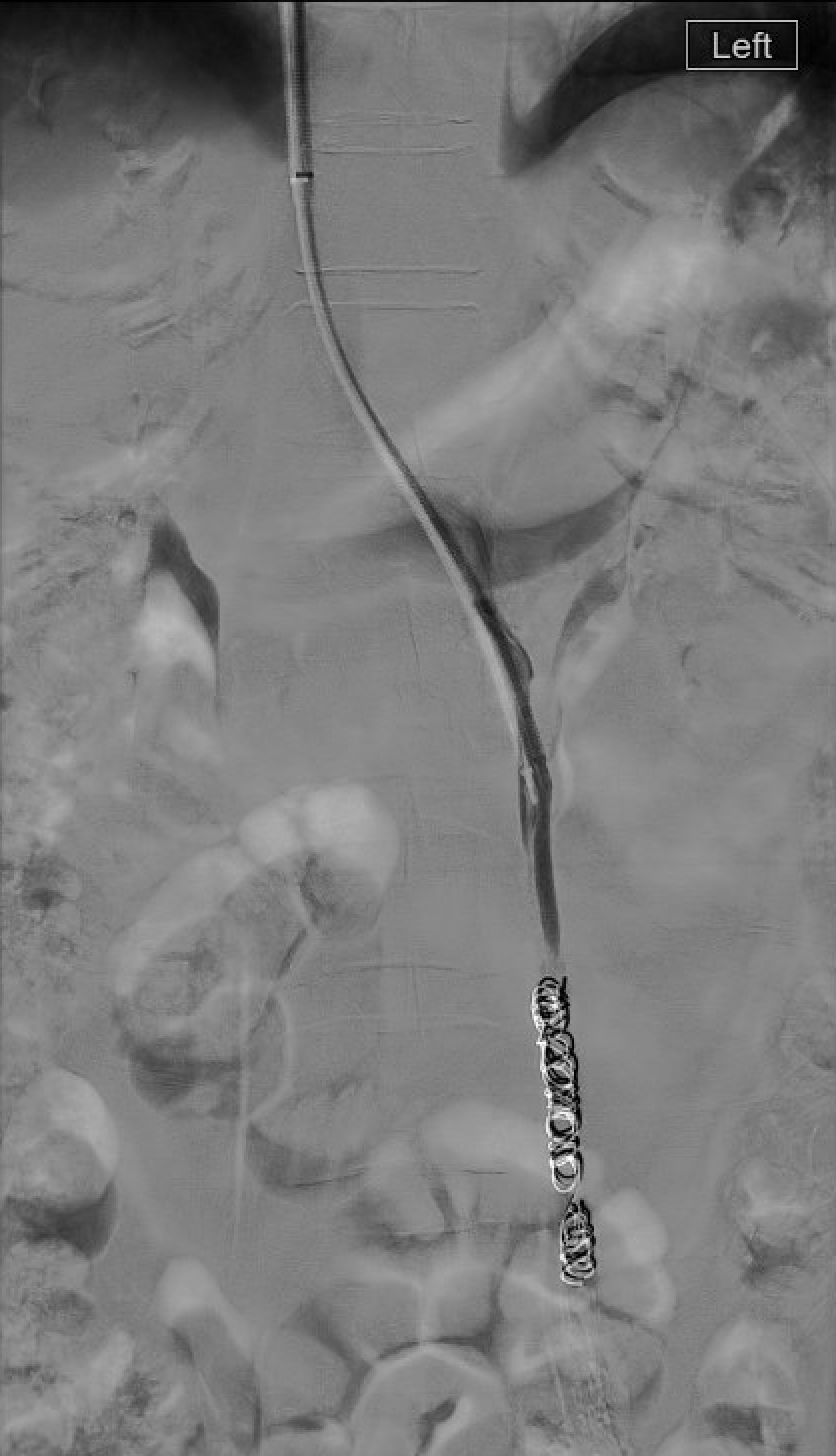

Step 3 — Embolization (Primary Reflux)

- Ovarian vein embolization: advance microcatheter to the pelvic inlet; deploy coils or inject foam sclerosant distally; retract and occlude the trunk up to ~1 cm from the renal vein ostium (prevents coil migration into renal vein or IVC).

- Sandwich technique (preferred): distal coils or foam → mid-trunk sclerosant → proximal coil anchor. Lowest recurrence in comparative series.

- Collateral occlusion: superselective catheterization and embolization of refluxing internal iliac tributaries — this step is critical and is the main determinant of long-term success.

- Completion venogram: confirm stasis, absence of reflux on Valsalva, and no non-target filling.

| Coils (pushable/detachable) | Proximal and distal anchors in gonadal vein trunk | Precise placement; sized 20–30% larger than vein diameter |

| Polidocanol or STS foam (3%, 1:4 air ratio) | Sclerose parauterine and pudendal varices | Penetrates small collaterals; coil + polidocanol foam combination shows 76% clinical effectiveness |